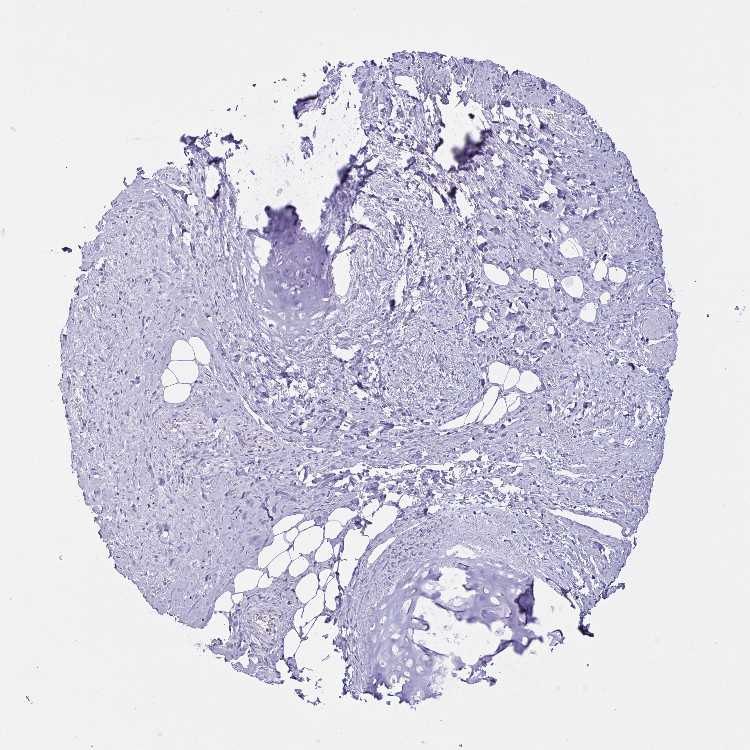

SOFT TISSUE 1 - Antibody stainingi

Antibody staining in the annotated cell types in the current human tissue is reported as not detected, low, medium, or high, based on conventional immunohistochemistry profiling in selected tissues. This score is based on the combination of the staining intensity and fraction of stained cells.

Each image is clickable and will lead to virtual microscopy that enables deeper exploration of all samples and also displays staining intensity scores, fraction scores and subcellular localization as well as patient and tissue information for each sample.

Antibody HPA058909

Chondrocytes Not detected

Fibroblasts Not detected